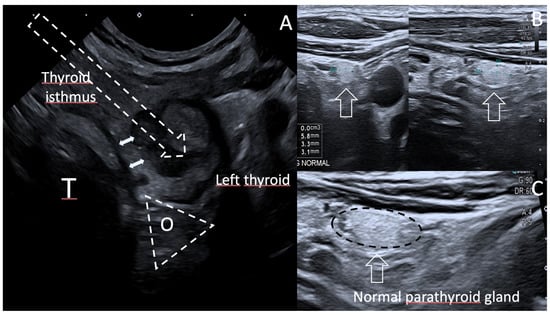

- Kim, S.J.; Na, D.G.; Noh, B.J. US features of normal parathyroid glands: A comparison with metastatic lymph nodes in thyroid cancer. Ultrasonography 2023, 42, 203–213. [Google Scholar] [CrossRef] [PubMed]